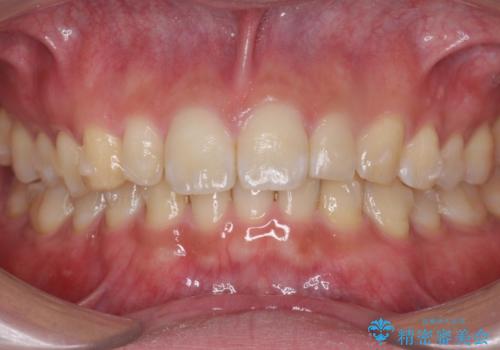

前歯のすき間 小さい歯がある 前歯の並びをきれいにしたい

- 前歯のすき間を気にして来院。

前から2番目の歯が小さく厚みがあったため(矮小歯)

矯正治療で1番目の歯を寄せて2番目の歯はセラミックで形をととのえています。